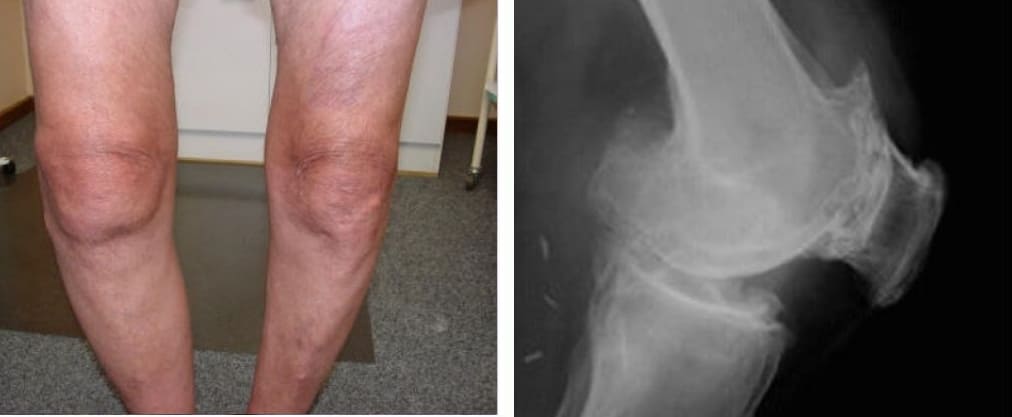

Mire esta radiografía. Es la columna de una persona de 44 años, pero parece la de un anciano. Antes, este tipo de daño aparecía después de los 60 años y, hoy, es muy común en personas de poco más de 40. Estos cambios progresan con la edad, y ignorarlos amenaza con una pérdida completa de movilidad.

Columna de un paciente de 44 años: todo comenzó con un dolor simple, pero en una semana apareció la hernia, y en dos semanas — desplazamiento de las vértebras, compresión de nervios y silla de ruedas.

Mire estas fotografías. Esto es lo que les sucedió a todos los que ignoraron los síntomas. Hoy, estas personas están completamente sin esperanza, y muchos de ellos no tienen a quién acudir en busca de ayuda. ¿Realmente, quiere un destino así?

Atrofia y fuerte curvatura de las articulaciones de las rodillas, dolor constante y agudo incluso con los movimientos más leves.

Atrofia del cartílago de la rodilla, necrosis del tejido, destrucción completa de la articulación e inevitable amputación.